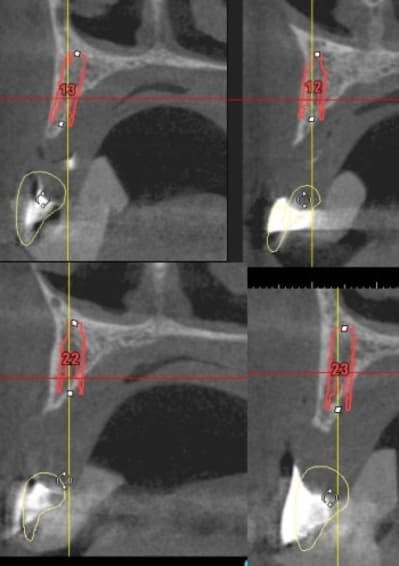

vis de cicatrisation sur une expansion réalisée en mars 09 à Sallanches implants en 13/14/15/18 pour une barre et PT.

Interessante car fracture de l'os vestibulaire y compris de la bosse canine, vitalos mais pas de vis d'ostéosynthese, et comme je sais que le doute est toujours present, ouverture large, avec décollement plus que necessaire pour controle.

sur l'implant en 14 une feuille d'os , en 13 un petit creux en mesio vestibulaire et 15 nickel.

il ne s'agit pas de montrer que cette technique est la seule, mais juste que dans ce cas tout va bien.

18/17 et 28/ 27 en flapless (4 SL )

le gros point noir c'est 15, je ne suis pas sur que la solution soit de poser un implant de suite.

13 et 12 ça va le faire il te restera 22 23 et 24.